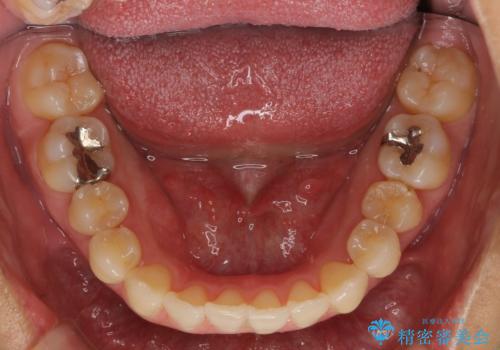

埋まっている奥歯を引っ張り出す インビザライン矯正

- インビザライン および ワイヤーによる部分矯正

埋まっている奥歯を並べることで、その後ろの倒れ込んだ歯を整直させることができました。

引っ張り出すことはマウスピース矯正では難しい為、埋まっている歯を並べるスペース確保と、引っ張り出すのに、ワイヤーを用いた部分矯正を行なっています。

上の歯はマウスピース矯正で、奥歯を後ろに下げて、左のかみ合わせのズレを直しています。

上下とも非抜歯で並べています。

埋まっていた歯をしっかり引っ張り出すことができ、また、前歯の見た目も非常に良くなりました。

ワイヤー矯正を奥歯の部分的に行なっただけで、治療の大半をマウスピース矯正で行うことができ、非常に喜んでいただきました。